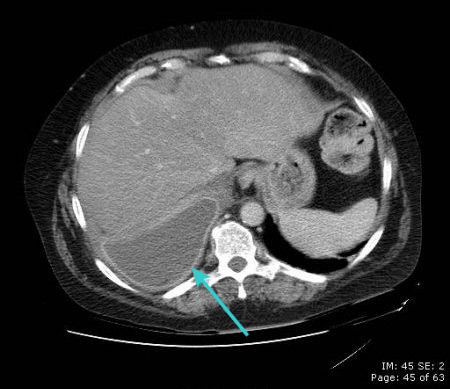

CT scan showing empyema with split pleura sign (enhancement of the thickened inner visceral and outer parietal pleura separated by a collection of pleural fluid)

From the collection of Dr Ami Rubinowitz; used with permission